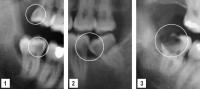

Impacted Wisdom Teeth

Impacted wisdom teeth can also adversely affect the attachment of adjacent teeth or be associated with cystic lesions.

- Horizontally impacted wisdom tooth adversely affecting attachment of second molar

- Extensive cystic development around impacted lower wisdom tooth